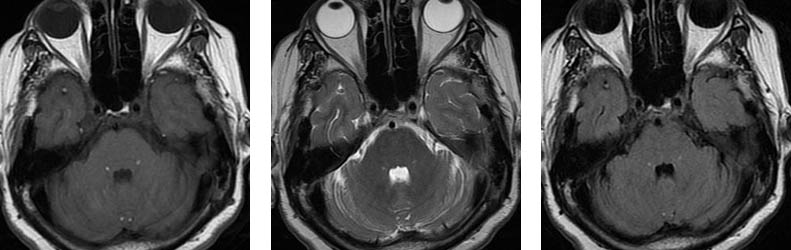

Üç farklı seviyeden aksiyal planda TlAG, T2AG ve FLAIR görüntüler Subaraknoid mesafelerde, özellikle BOS'un hipointens izlendiği TlAG ve FLAIR sekanslarda dağınık milimetrik hiperintens od aklar dikkati çekmektedir.

Pantopaque yağa benzer şekilde kısa T1 ve T2 reIaksasyon sürelerine sahiptir. Bu nedenle Tl ve T2AG'Ierde hiperintens olarak izIenirIer ve özellikle BOS mesafelerinin baskılandığı T1AG ve FLAIR sekanslarında dikkati çekerler.